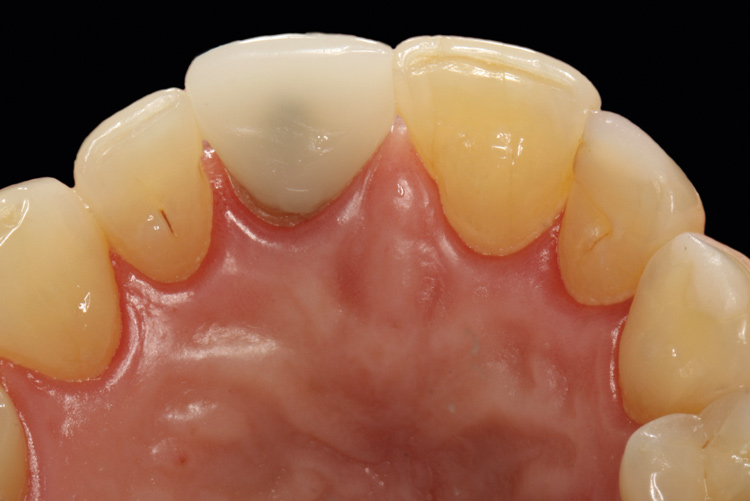

(26.) Facial and occlusal views of the soft-tissue contour achieved after 3 months of provisionalization. The tissue is thick with a harmonious gingival contour and zenith position.

Figure 26

(27.) Facial and occlusal views of the soft-tissue contour achieved after 3 months of provisionalization. The tissue is thick with a harmonious gingival contour and zenith position.

Figure 27

The patient was postoperatively evaluated at 1-, 2-, 4-, 8-, and 12-week recall appointments. The sutures were removed at the 2-week appointment, and the patient was instructed to rinse twice daily and avoid brushing the anterior maxilla. Prior to provisionalization of the implant, the site was allowed to heal for 6 months, during which time the patient was temporized with another Maryland bridge. At the 6-month recall appointment, full mouth periodontal maintenance was completed, and an implant-retained acrylic provisional restoration was placed (Figure 23 through Figure 25). An acrylic provisional restoration allows for soft-tissue attachment while preventing apical migration of the gingival margin. After a 3-month provisionalization period, the final prosthesis was delivered (Figure 26 through Figure 29), and the patient was scheduled for ongoing 3-month recall appointments for periodontal maintenance.